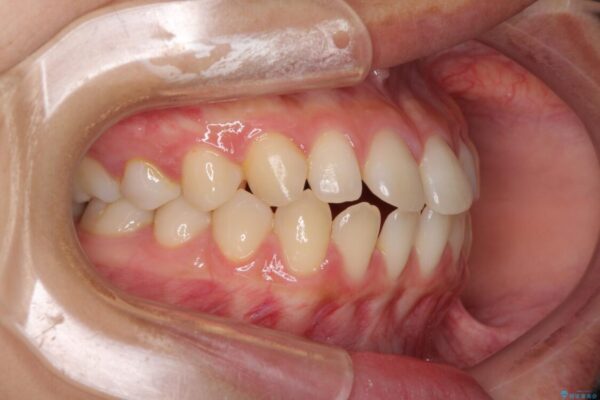

治療前

• 隙間だらけの歯列 インビザラインで改善 治療前画像